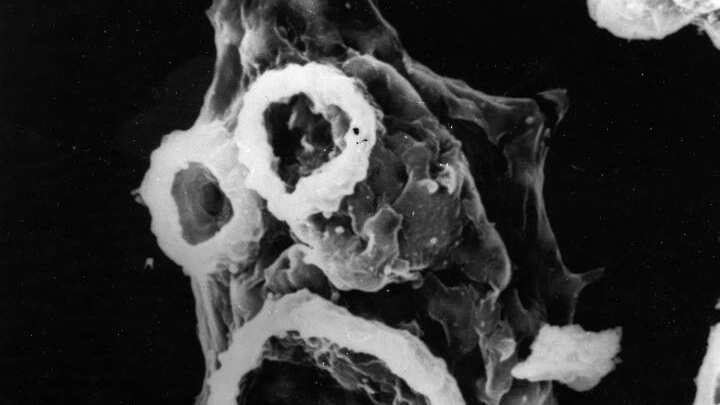

El caso de meningoencefalitis amebiana primaria (MAP) provocada por el parásito Naegleria fowleri, se registró en la localidad bonaerense de general Andrés.

Cabe mencionar que la MAP es una infección que destruye los tejidos cerebrales producida por la mencionada ameba, que puede estar presente en cursos de agua dulce contaminados.